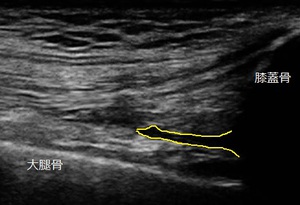

右ひざ 超音波長軸像 同部 1週間後

超音波観察の結果、右膝蓋骨(お皿)の上部には内出血が貯留している様子が認められました(上部左画像の

黄色線内)。

いきます。1週間後、施術効果を客観的に評価するために超音波観察を実施し、内出血の減少を確認しました

(上部右画像の黄色線内)。